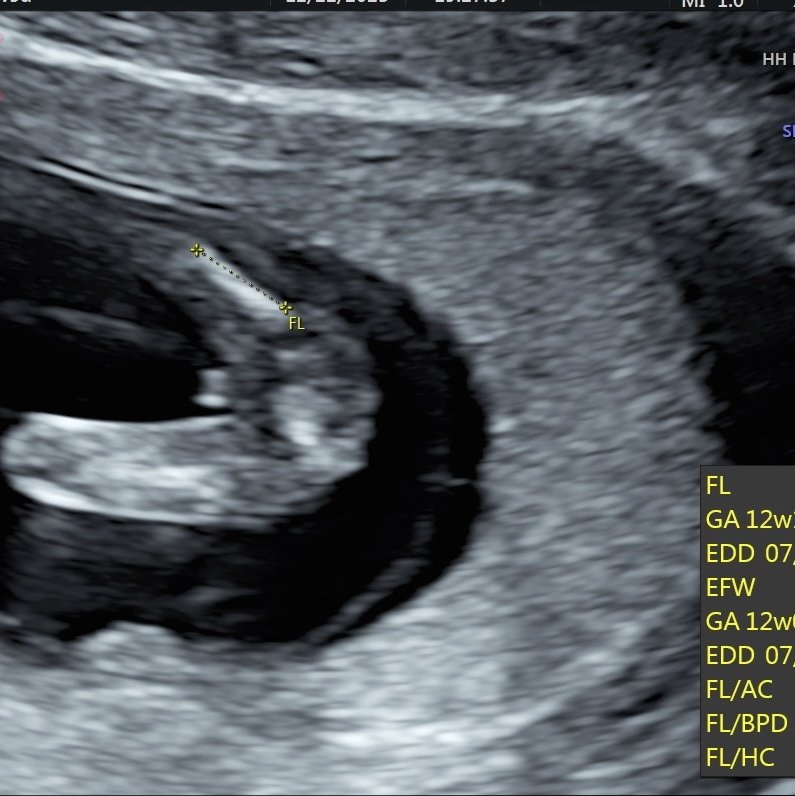

超音波是男寶還女寶

上週去照第一孕期高層次

腿腿中間時而凸時而不凸

好奇是弟弟還是妹妹> <